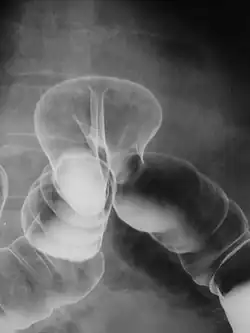

Для исследования органов желудочно-кишечного тракта применяются как взвеси нерастворимых в воде веществ (сульфат бария), так и йодсодержащие вещества. Нерастворимые контрастные вещества в целом более безопасные, т.к практически не взаимодействуют с тканями организма. Однако, в некоторых случаях предпочтение отдаётся водорастворимым контрастным веществам — например, при подозрении на перфорацию полого органа или кишечную непроходимость.

В зависимости от метода исследования, контрастные вещества отличаются по своему составу и способу введения. История медицинских контрастных веществ начинается в 1931 году с создания первых поглощающих рентгеновские лучи и безвредных для организма препаратов. Наиболее распространённым в классической рентгенологии рентгеноконтрастным веществом является сульфат бария. Главным недостатком этого вещества является его нерастворимость в воде, в связи с чем невозможно использовать сульфат бария там, где есть угроза попадания его за пределы полого органа (в брюшную полость, в кровоток и т. д.). В качестве естественного контрастного вещества используется атмосферный воздух, который, в отличие от сульфата бария, является рентгенонегативным (поглощает рентгеновское излучение слабее тканей тела, создавая рентгенологический эффект «просветления»). Такой способ контрастирования называется пневмографией. Для этой цели может быть использован любой газ. Так, например, для двойного контрастирования желудка больному даётся сода, и образовавшийся углекислый газ раздувает желудок, в который предварительно был введён сульфат бария — это позволяет осмотреть рельеф слизистой и состояние его стенок. В середине 80-х годов XX века были созданы контрастные препараты для МРТ и КТ.